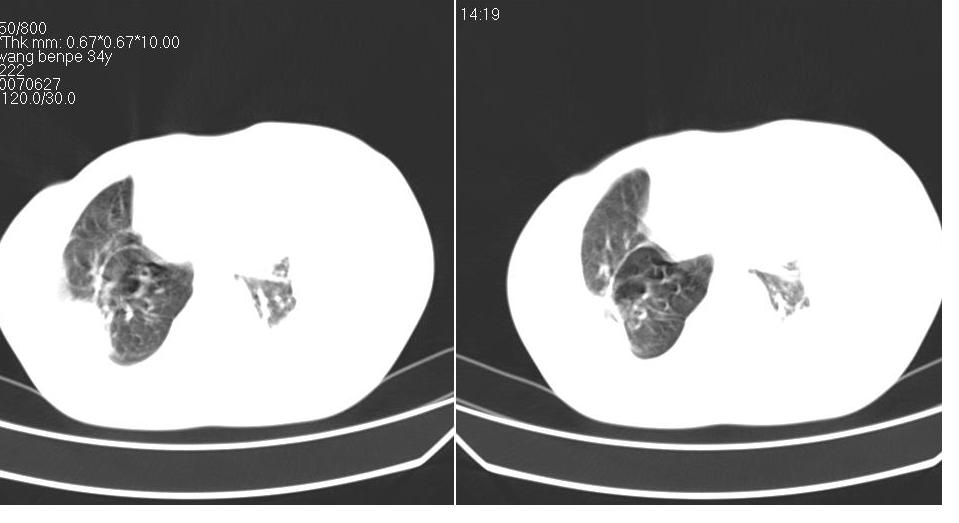

以下是引用苯小孩在2007-6-27 15:09:00的发言:[br]考虑:1、右肺继发性肺结核.2、双侧包裹性积液<胸腔及叶间>3、双侧局部胸膜增厚.[br]建议胸水化验检查.

以下是引用yanghaochen88在2007-6-27 15:08:00的发言:[br]双肺上野散在粟粒状影、包裹性积液、胸膜增厚粘连、叶间积液---tb,至于分型还得结合病史体征细究妥当些。